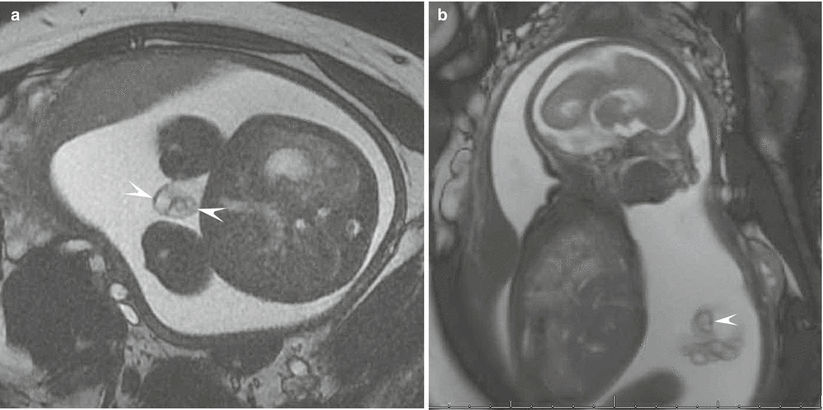

Imaging protocols

Imaging protocols 115 фотографий